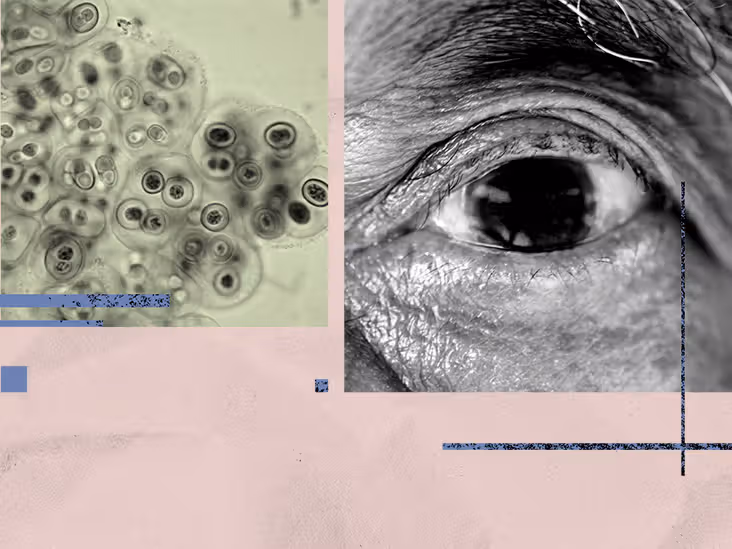

Share on PinterestA new study suggests that targeting stem-like cancer cells could prevent colorectal cancer ...